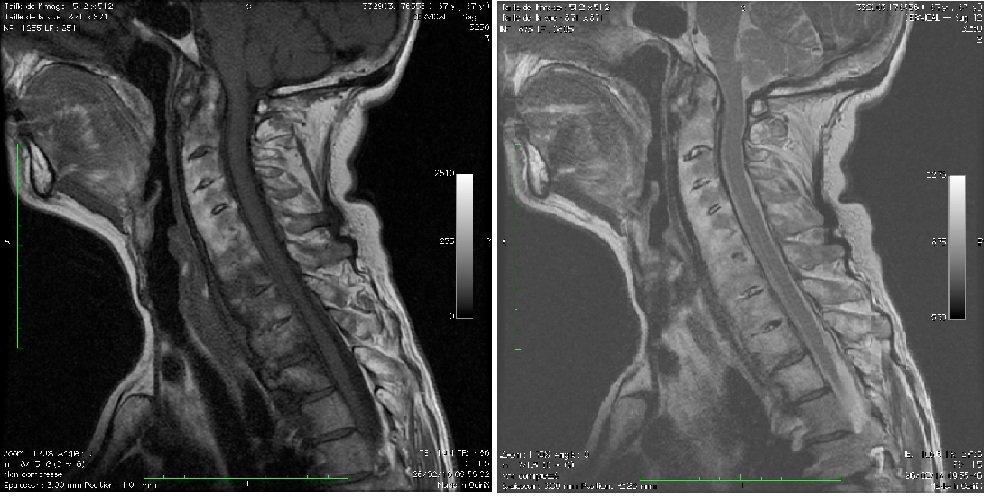

Atteinte rachidienne cervicale évoluée dans le cadre d'une spondyloarthrite axiale radiographique